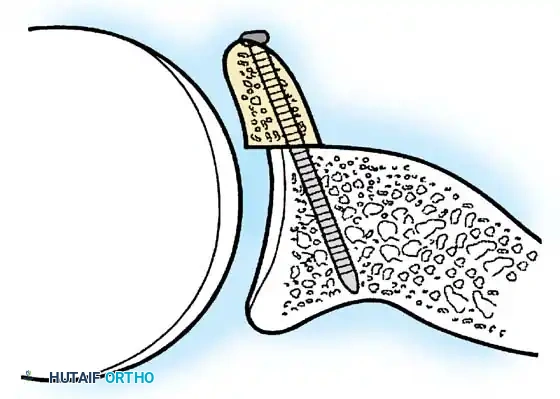

- Anchor Placement: Suture anchors (typically 3 to 4) are placed along the articular margin of the anteroinferior glenoid (from the 5:30 to 3:00 positions for a right shoulder). Anchors must be inserted at a 45-degree angle to the articular surface to maximize pullout strength and avoid joint penetration.